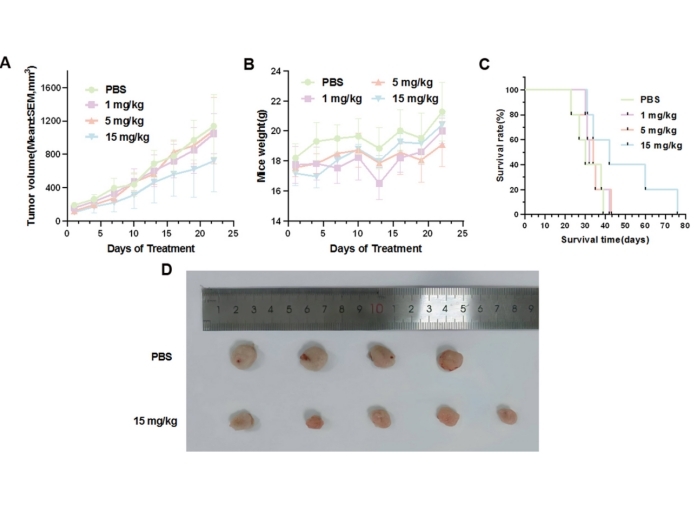

本发明提供2-吲哚甲酸在制备肿瘤靶向治疗药物中的应用。通过计算机辅助药物设计和分子对接优化,2-吲哚甲酸显示出对HER2激酶结构域的高结合能。在NCI-N87细胞荷瘤裸鼠模型中,2-吲哚甲酸(15 mg/kg)显著抑制肿瘤生长,且未引起明显体重下降或器官毒性。本发明为HER2靶向治疗提供了具有临床转化潜力的先导化合物。